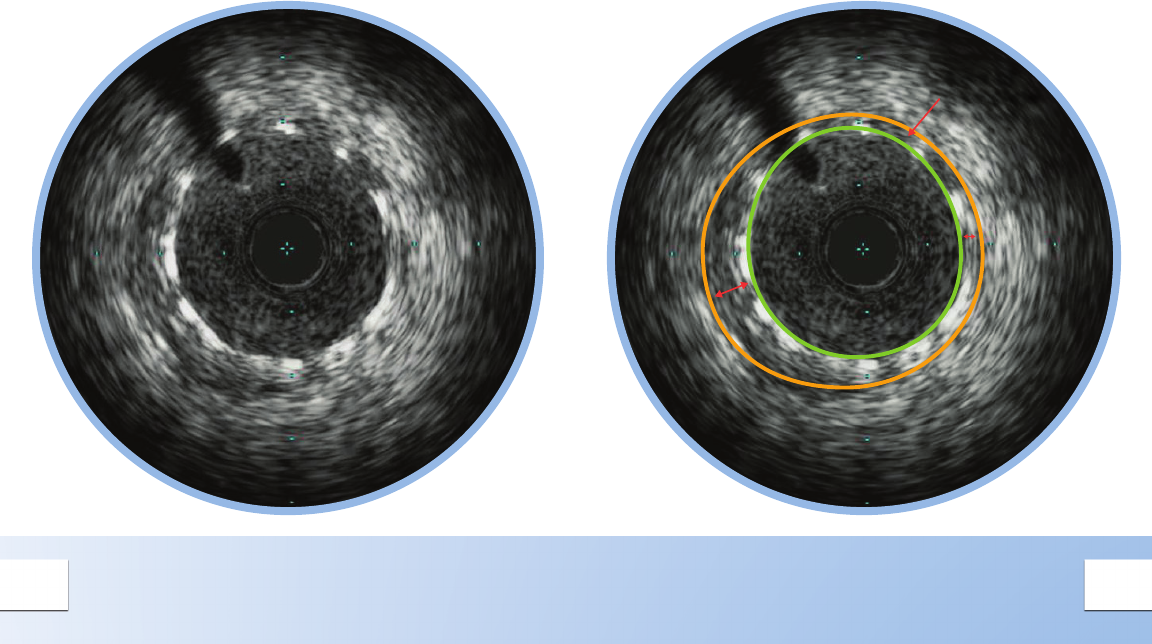

FIBROUS PLAQUE

These plaques have an intermediate echogenicity

between soft (echolucent) atheromas and highly

echogenic calcic plaques.

Fibrous plaques exhibit little or no

acoustic shadowing.